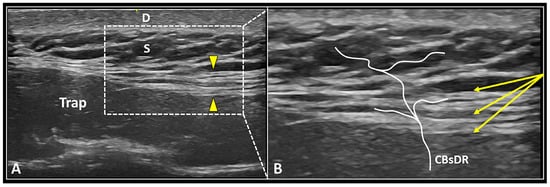

- Ricci, V.; Ricci, C.; Mezian, K.; Naňka, O.; Özçakar, L. Trapezius muscle and the cutaneous branches of spinal nerves: Sonographic/anatomic discussion on myofascial pain and superficial injections. Pain Med. 2022, pnac125. [Google Scholar] [CrossRef]

- Ricci, V.; Ricci, C.; Cocco, G.; Donati, D.; Farì, G.; Mezian, K.; Naňka, O.; Özçakar, L. From histology to sonography in skin and superficial tissue disorders: EURO-MUSCULUS/USPRM* approach. Pathol. Res. Pract. 2022, 237, 154003. [Google Scholar] [CrossRef]

| Deep Fascia/CBsDR | Fascial hydro-dissection | Seeding technique to optimize layer-by-layer dissection |